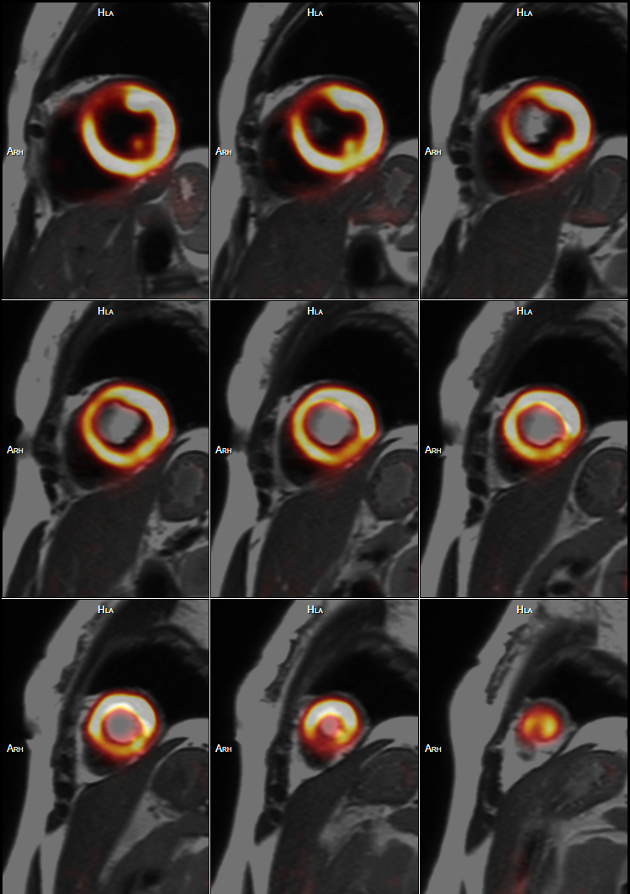

在心血管疾病診斷方面,PET/MR通過(guò)多參數(shù)、多平面和多序列成像可清晰顯示解剖結(jié)構(gòu)、運(yùn)動(dòng)功能、血流灌注和組織特性,通過(guò)MR序列對(duì)PET圖像進(jìn)行呼吸運(yùn)動(dòng)校正,實(shí)現(xiàn)時(shí)間和空間上最佳配準(zhǔn)的一站式評(píng)估,對(duì)心血管疾病的診斷與治療具有重要的意義。PET/MR可以進(jìn)行心肌灌注及心肌活力評(píng)價(jià)、風(fēng)險(xiǎn)分層、預(yù)后、指導(dǎo)治療,心臟動(dòng)脈硬化斑塊成像,評(píng)價(jià)瘢痕范圍(LGE)、左室功能,評(píng)價(jià)炎性心肌病及浸潤(rùn)性心肌病的活動(dòng)狀態(tài),心肌淀粉樣變的評(píng)價(jià)